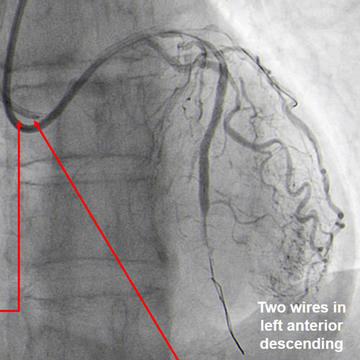

Miracle exchanged with floppy wire to LAD. Guide wires position checked via controlateral injection (Figure 5.2).

Guide wires position via contralateral injection (Figure 5.2)